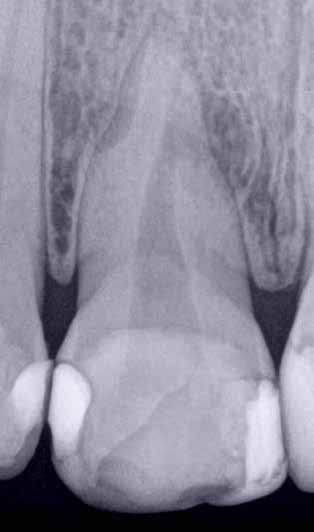

Hölgy páciensem az első konzultáció során tipikus kórtörténetet vázolt fel: Gyermekkora óta szeretett volna fogszabályozó készüléket, hiszen mindig is zavarta a class 2-es eltérésnél tipikusan jellemző nagy overjet (1-3. képek), és természetesen az ezáltal kifelé álló felső metszőfogai, részben a felső metszők protrúziója, részben pedig a disztálisan elhelyezkedő mandibula miatt. Annak ellenére, hogy több fogszabályozó szakorvosnál is járt az évek során, de mivel saggitális eltérése és az alsó metszőfogak torlódása miatt négy kisőrlőfog extrakcióját, illetve emellett sokszor állcsont műtétet is javasoltak neki, nem vágott bele a kezelésbe (4-5. képek).

A fogorvosa – nagyon helyesen – felhívta a figyelmét, hogy parodontális státusza is valószínűsíthetően romlani fog az eltérése miatt, újabb kört futott, immár 39 évesen, de még mindig premoláris fogak húzása és állcsontműtét nélkül szerette volna a fogszabályozást.